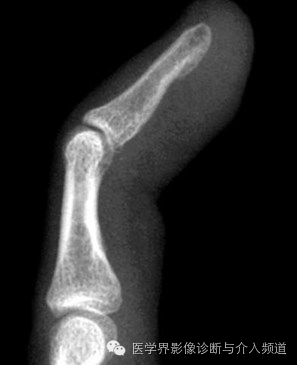

1、Mallet 指

远节指间关节屈曲畸形。又称篮球指,远节指间关节屈曲畸形,由伸趾肌腱断裂造成,常由打篮球中直接撞击手指引发。